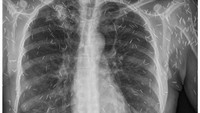

Bocah berusia dua tahun di Peru secara tidak sengaja menelan delapan jarum suntik saat ibunya sedang bekerja. (San Martin Regional Government)